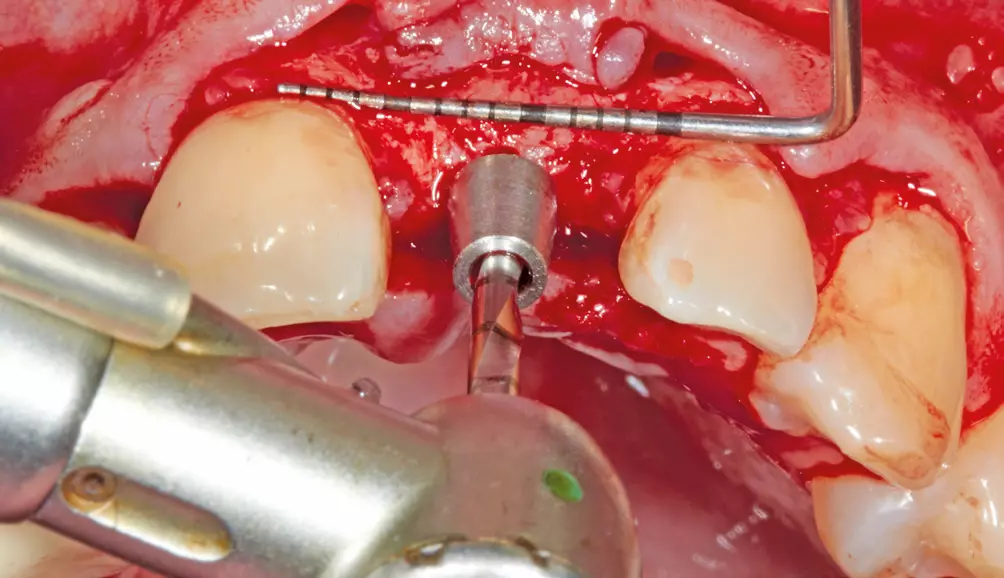

Nach einer Einheilphase von drei Monaten konnte implantiert werden. Es sollte eine okklusal verschraubte Krone verwendet werden. Die Entscheidung des Implantatsystems fiel auf ein ELEMENT Implantat von Thommen Medical, da es über einen sehr kleinen Schraubenkanal verfügt und damit eine gute prothetische Versorgung – gerade im Frontzahnbereich – ermöglicht. Hier hat man es häufig mit Problemen der Einschubrichtung des Implantates zu tun und ein kleiner Schraubendurchmesser schafft Platz, um eine Verschraubung möglich zu machen. Für die Implantation erfolgte in Lokalanästhesie eine krestale, leicht lingual versetzte Schnittführung unter Erhaltung eines einige Millimeter breiten Streifens befestigter Mukosa. Das Implantat wurde in korrekter Position ca. 3-4 mm oberhalb der Schmelz-Zement-Grenze sowie ca. 2 mm oral von der Verbindungslinie der benachbarten Wurzeloberflächen und mit einer Implantatachse palatinal von der geplanten Schneidekante gesetzt (Abb. 7 und 8). Danach wurde ein steriler Abformpfosten für eine offene Abformung aufgeschraubt. Zur Anfertigung des Index wurde Triad Gel (Triad Gel Clear Colorless, Dentsply International, York, PA, USA) benutzt. Dazu wurde das Material in eine sterile 2-ml-Einmal-Spritze gefüllt und auf den Abformpfosten und beide Nachbarzähne aufgetragen. Die Aushärtung erfolgte mit einer in eine sterile Folie eingepackten Polymerisationslampe.

Nach der Heilungsphase war für einen Aufbau der vestibulären Lamelle ein Knochentransplantat aus dem Kieferwinkel erforderlich. Dies sorgte für eine gute und gleichmäßige Ausformung des Vestibulums und es bestand die Möglichkeit, das Implantat an die gleiche Stelle wie die Zahnwurzel zu setzen (Abb. 5 und 6).